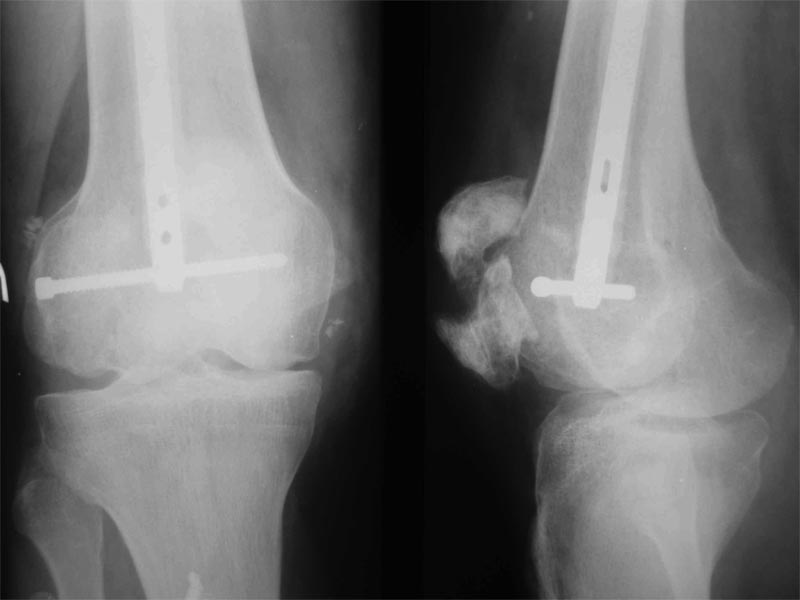

Уважаемые коллеги! Пациент получил травму около 1 года назад, выполнялся остеосинтез по поводу переломов лучевой, бедренной, плечевой костей.

Обратился в связи с выраженной контрактурой в коленном суставе (сгибание 10-15 град)и практически отсуствием самостоятельного отведения плеча. Снимки представлены. Планируем выполнить реостеосинтез плеча (скорее всего этим же стержнем, так как другого нет) с коррекцией положения отломков в проксимальном отделе и сближением отломков в области диафиза.

По надколеннику пока одна идея - его удаление.

- приведет ли удаление надколенника и релиз сустава к существенному улучшению функции?